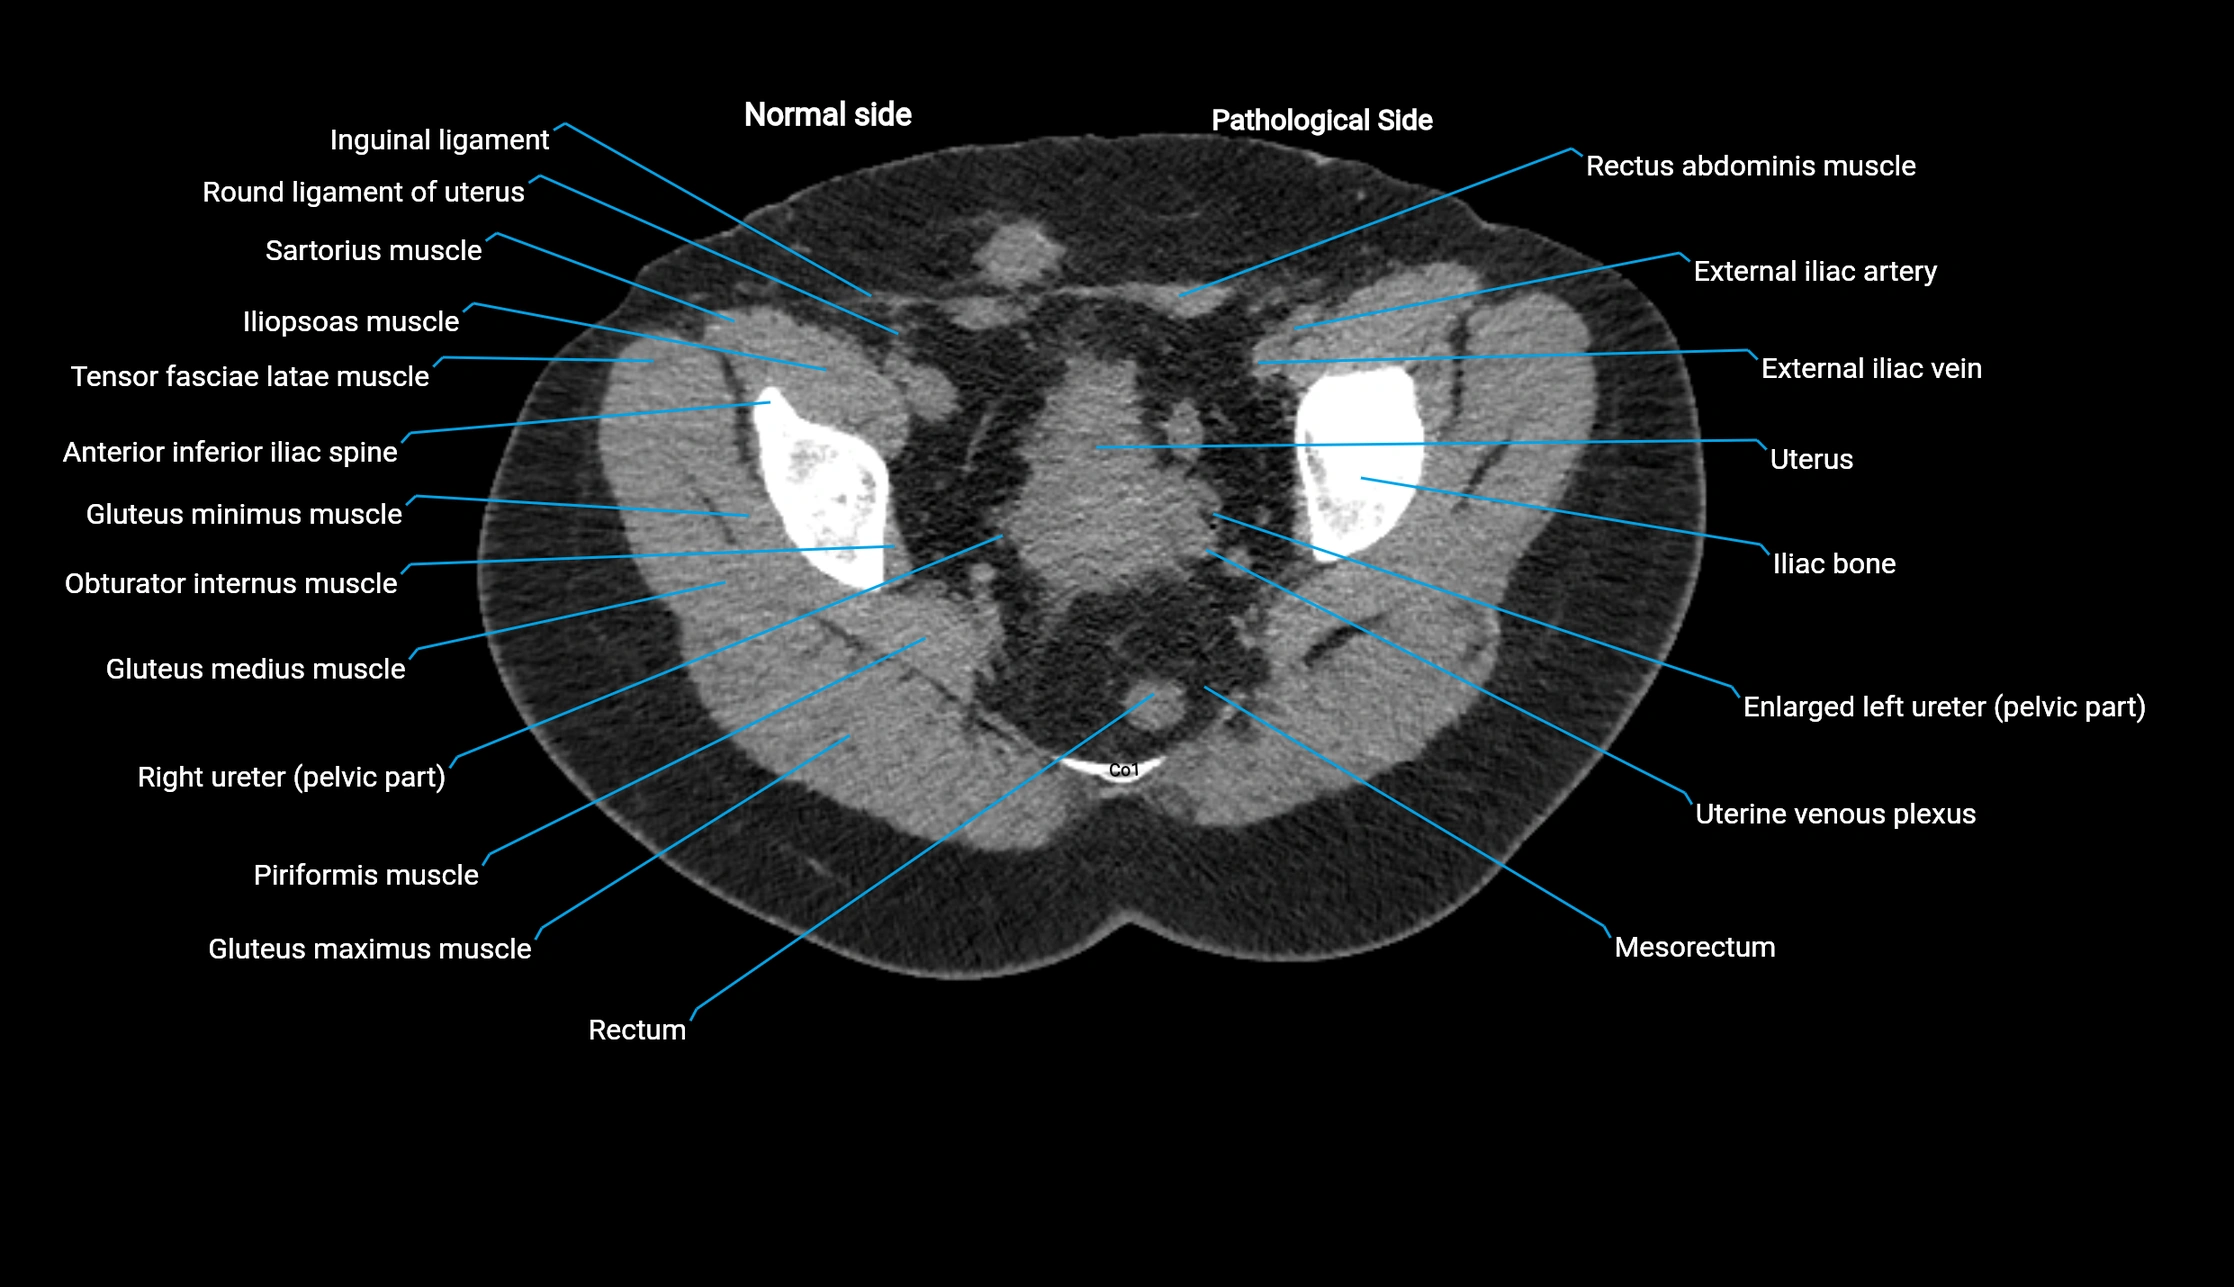

CT image

image